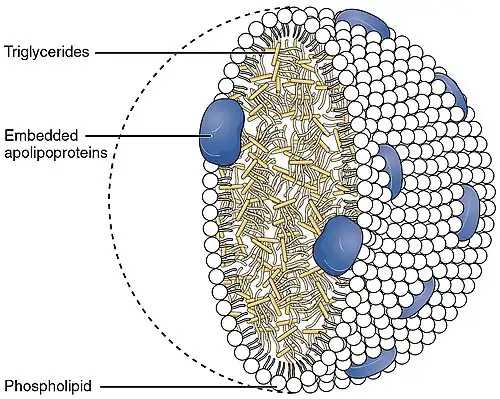

The Framingham Heart Study and other epidemiological studies have found a correlation between lipoproteins and cardiovascular disease (CVD).[7] Lipoproteins are generally a major target of study in lipidology since lipids are transported throughout the body in the form of lipoproteins.[2]

A class of lipids known as phospholipids help make up what is known as lipoproteins, and a type of lipoprotein is called high density lipoprotein (HDL).[8] A high concentration of high density lipoproteins-cholesterols (HDL-C) have what is known as a vasoprotective effect on the body, a finding that correlates with an enhanced cardiovascular effect.[9] There is also a correlation between those with diseases such as chronic kidney disease, coronary artery disease, or diabetes mellitus and the possibility of low vasoprotective effect from HDL.[10]

Another factor of CVD that is often overlooked involves the concentrations of low-density lipoproteins (LDL) and very low-density lipoproteins (VLDL). These are often seen at higher than expected and necessary levels in the body due to food uptake, family history, and a person's metabolic rate. There is a correlation between these increased levels and stroke, heart attack, and mortality.[11]